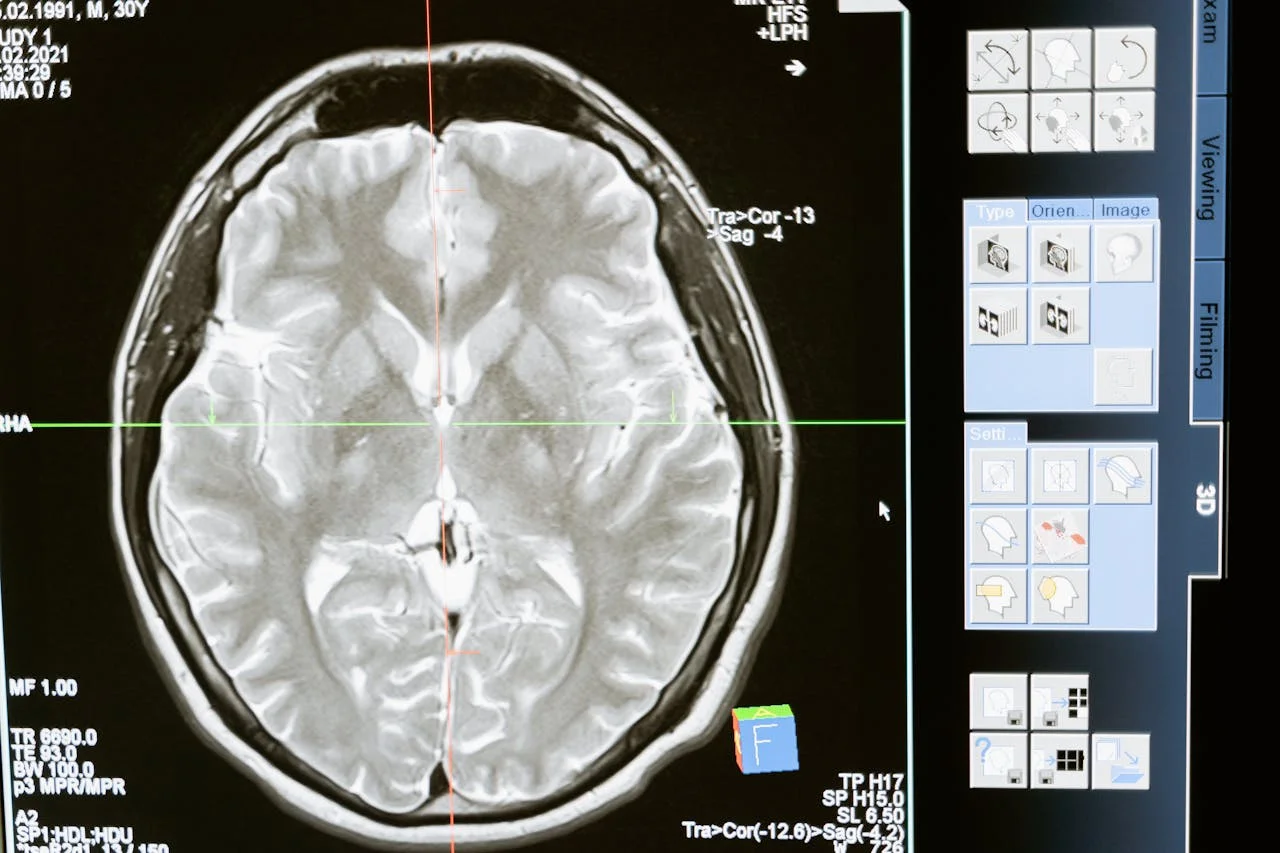

The field of neurology is on the brink of transformation as Hyperfine, Inc. (Nasdaq: HYPR) announces the enrollment of its first patients in the groundbreaking NEURO PMR (Neurological Evaluation in the Office with Portable MRI) study. This real-world research initiative aims to evaluate the clinical utility and patient experience of AI-powered portable MRI systems in neurology offices, addressing a critical gap in modern healthcare delivery. As the pioneer behind the first FDA-cleared portable MR brain imaging system—the Swoop® system—Hyperfine continues to redefine accessibility and affordability in advanced brain imaging.

Neuroimaging has long been an essential tool in diagnosing and managing neurological conditions. However, traditional high-field MRI systems are often inaccessible to private neurology practices due to their high costs, complex siting requirements, and the need for specialized personnel. On average, neurologists order 500 MRIs annually, yet most practices lack the infrastructure to perform these scans in-office. This limitation forces patients to travel to hospitals or imaging centers, creating delays and inconveniences that can hinder timely diagnosis and treatment.

The NEURO PMR study seeks to address this challenge by exploring how AI-powered portable MRI technology can integrate seamlessly into neurology offices. Conducted in collaboration with two leading private neurology practices—the DENT Neurologic Institute and Texas Neurology—this multi-center, prospective observational study will assess the performance of portable ultra-low-field MRI compared to conventional high-field MRI. The study focuses on pathology findings, clinical utility, and patient satisfaction, with a target enrollment of 100 patients and completion expected by year-end.

The Hyperfine Swoop® system represents a paradigm shift in medical imaging. Designed with simplicity and portability in mind, it eliminates many barriers associated with traditional MRI systems. Unlike high-field MRIs, which require costly infrastructure such as helium cooling and shielded rooms, the Swoop® system operates on a plug-and-play model, making it easy to deploy directly in exam rooms. Additionally, no specialized technologists are needed to operate the device, further reducing overhead costs for practices.

For patients, the benefits are equally compelling. Portable MRI systems reduce wait times, eliminate the need for additional appointments, and create a more comfortable imaging experience. With advanced AI-powered image enhancement, the Swoop® system delivers high-quality scans comparable to those produced by traditional high-field MRIs.

The launch of the NEURO PMR study marks a pivotal moment in the evolution of neuroimaging. As Hyperfine partners with leading neurology practices to validate the efficacy of its AI-powered portable MRI technology, the company is paving the way for a future where advanced imaging is no longer confined to large hospitals or specialized centers.

By making brain imaging more accessible, affordable, and patient-centered, Hyperfine is not only addressing current gaps in neurology care but also setting new standards for innovation in healthcare delivery. As the study progresses, its findings could reshape how neurology practices operate, ultimately benefiting patients and providers alike.

In an era where technology continues to drive progress in medicine, the Hyperfine Swoop® system stands out as a beacon of hope for improved accessibility and equity in neuroimaging. Stay tuned for updates on the NEURO PMR study as it moves closer to unlocking the full potential of portable MRI technology in neurology offices worldwide.